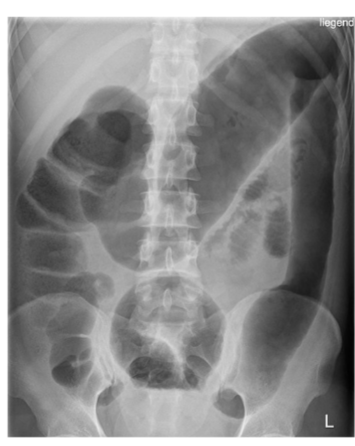

UC: Toxic megacolon

• Large bowel obstruction; loss of haustra